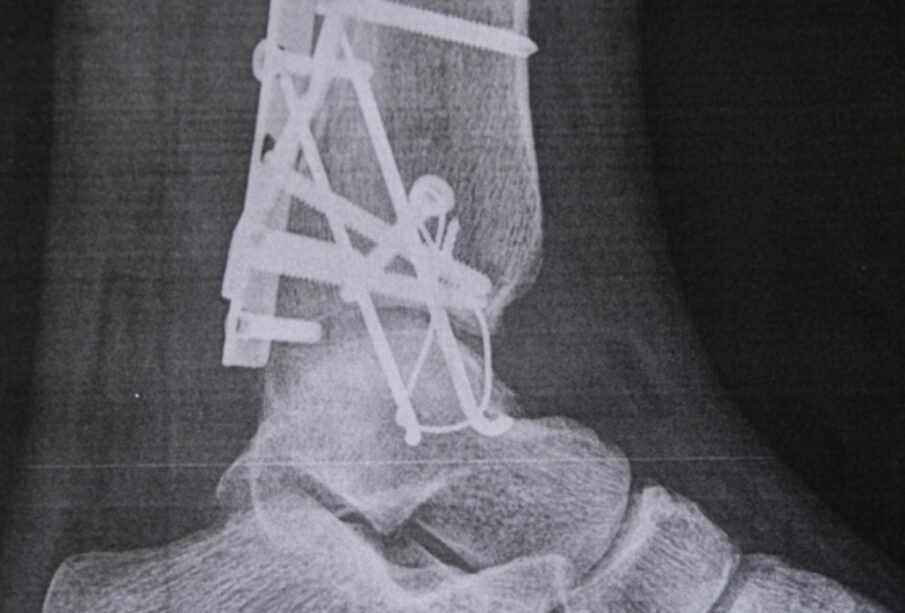

- Smagākos gadījumos skriemeļu saaugšana (ankiloze), kas būtiski ierobežo kustības.